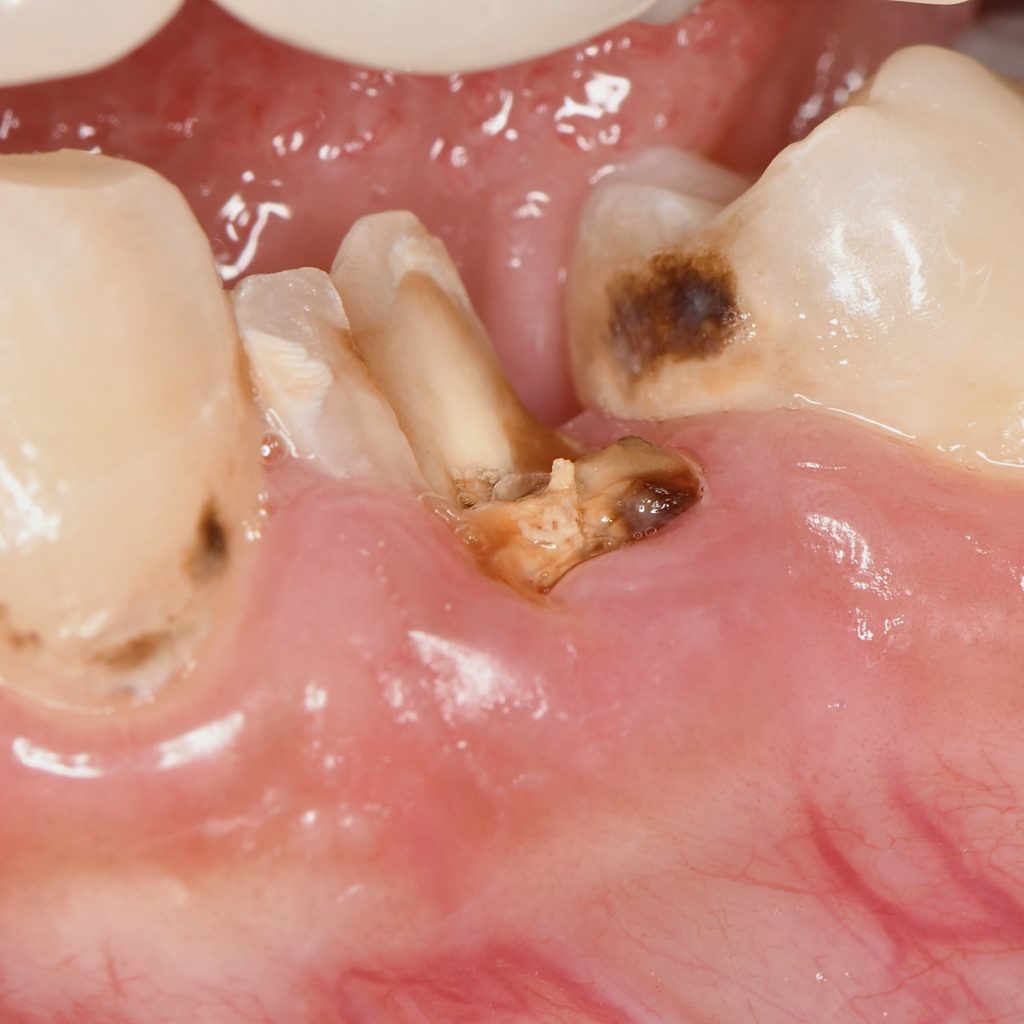

In this case, lower premolar ( 4) was treated previously with unsuccessful Endodontic treatment .

We isolate the tooth with rubber dam and Endodontic retreatment was done with Bioceramic sealer and single cone since it’s viable option for obturation

Rubber dam isolation

Obturation with Bioceramic sealer and single cone